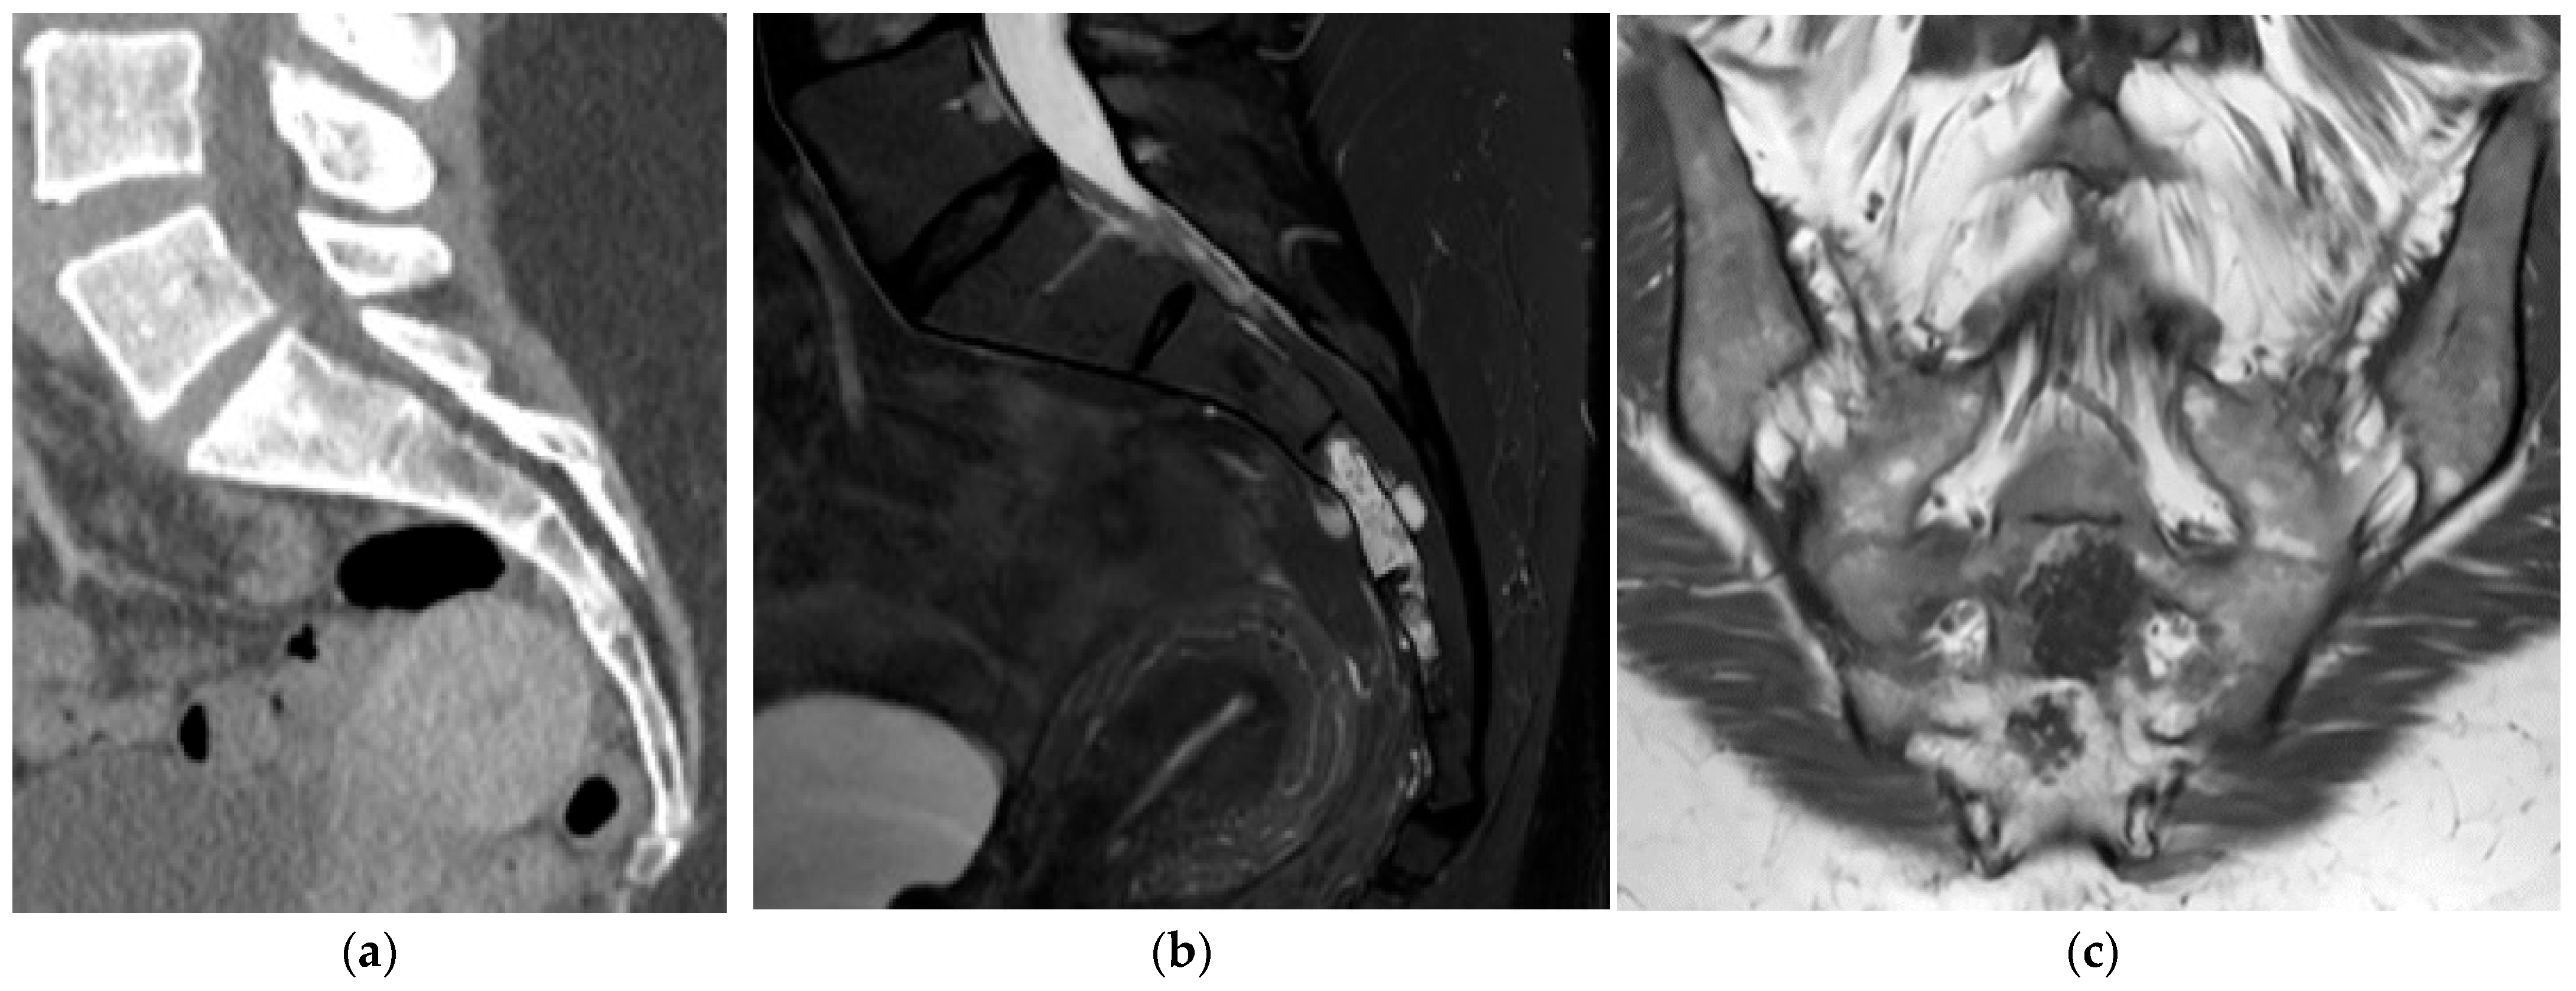

2.3.2. Chordoma